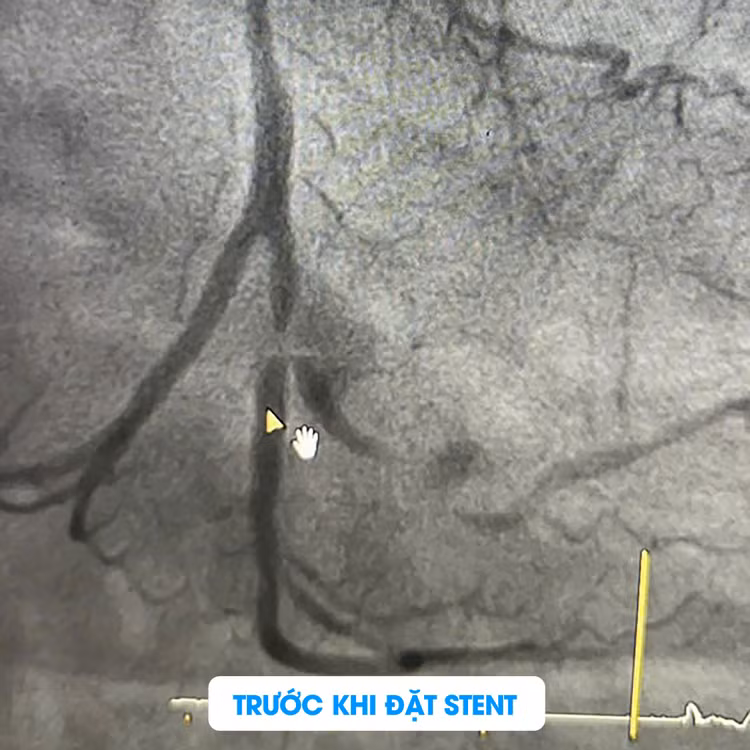

Sau khi nhập viện, bệnh nhân đã được tiến hành chụp mạch vành qua da để xác định tình trạng tắc nghẽn và xơ vữa. Kết quả chụp cho thấy bệnh nhân có tổn thương cả 3 nhánh động mạch vành với các mức độ khác nhau:

Thân chung động mạch vành trái (LM): Hẹp 30%.

Động mạch liên thất trước (LAD): Hẹp 40 - 50% ở đoạn gần, 40% ở đoạn giữa và xa, có nhiều vôi hóa.

Động mạch mũ (LCx): Hẹp 60% ở đoạn gần và hẹp nặng tới 99% tại đoạn xa ở vị trí chia đôi, có vôi hóa nhiều.

Động mạch sau (PDA): Hẹp 60%.

Sau khi hội chẩn kỹ lưỡng và cân nhắc đến các bệnh lý nền của bệnh nhân, bác sĩ Peter và các cộng sự đã quyết định thực hiện can thiệp nong đặt stent tại động mạch LCx, đoạn gần (LCx(d)), nơi có mức độ tổn thương hẹp nặng và nguy hiểm. Quy trình này giúp tái thông dòng máu đến vùng cơ tim bị thiếu máu, ngăn ngừa nguy cơ nhồi máu cơ tim tái phát.